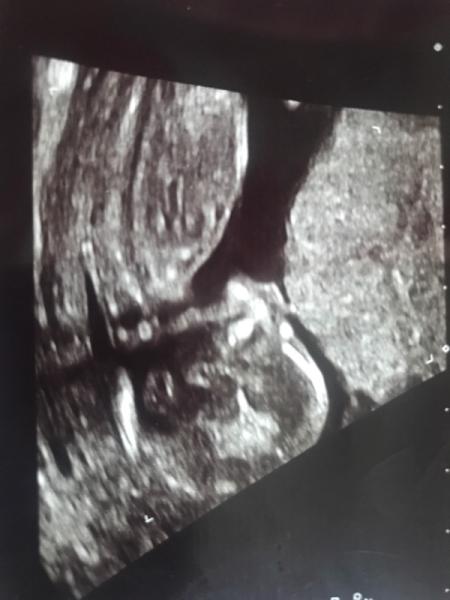

Wir haben heute auch das Geschlecht unseres Babys erfahren und wir sind Team rosa Ich hatte ein wenig auf einen jungen gehofft, aber spielt ja bei dem ersten nicht wirklich eine Rolle! Gesund ist unsere kleine Maus und das ist das wichtigste

Bild zu Outing - Forum für Januar - Mamis